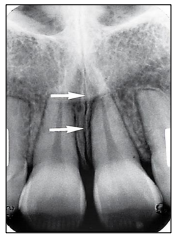

Observe a imagem a seguir.

Como se chama a estrutura anatômica vista nesta radiografia periapical e indicada pelas setas?